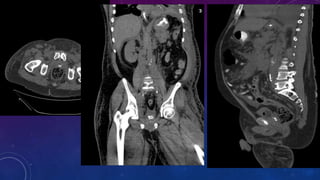

SPOT 3 ORGANS

WITH

CALCIFICATIONS

Gall stone

Calcific pancreatiits

Penile calcification

• #73 Gall stone Calcific pancreatiits Penile calcification